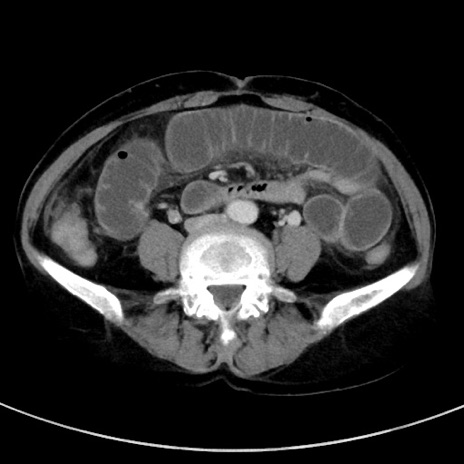

冠状断像

【症例】70歳代女性

【主訴】下腹部痛・嘔吐

【現病歴】2日前より腹痛あり。昨日嘔吐あり。症状改善しないため来院。

【既往歴】胃GISTに対して胃部分切除後。

【身体所見】BT 37.1℃、BP 128/77mmHg、腹部:平坦・軟、下腹部に圧痛あり。

【データ】WBC 10200、CRP 0.31